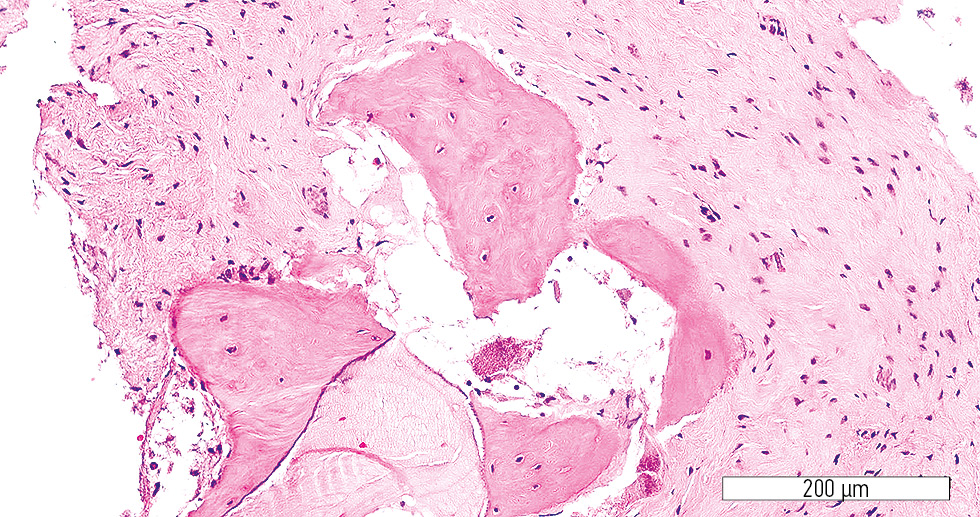

In the control group, numerous bone chip fragments were observed. Neither an obvious stromal component nor structured bone trabeculae were identified (Fig. 5). Isolated regions of active stromal component with pronounced vascularization were present. The bone trabeculae appeared immature, with osteoblasts and newly formed lacunae containing osteocytes (Fig. 6).

Fig. 5. Numerous bone fragments without stromal component or newly formed trabeculae (control group). Hematoxylin-eosin stain; original magnification ×200.